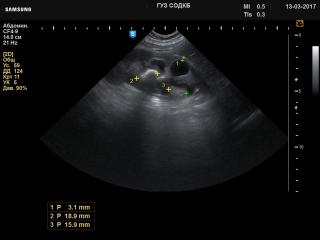

Kidney - stones and dilated renal pelvis, B-mode

H60. Kidney - stones and dilated renal pelvis, B-mode.